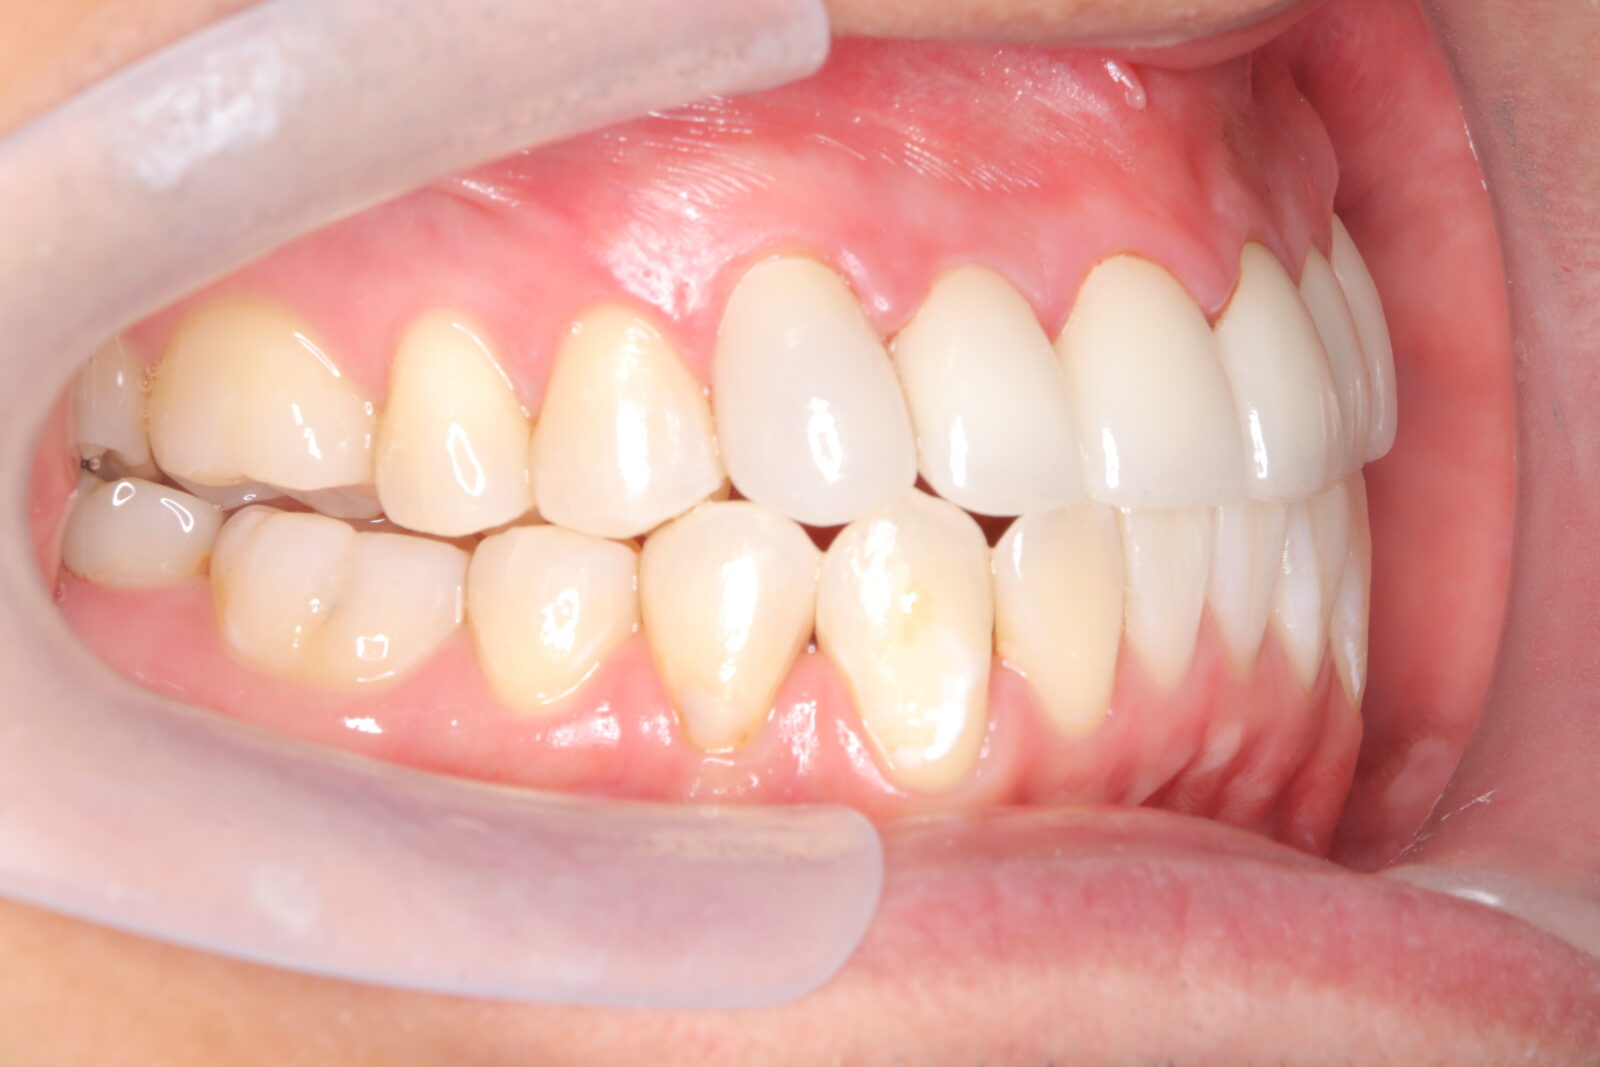

インビザライン(全体矯正)+ホワイトニングコース+セラミック治療の症例

過去にワイヤー矯正で治せなかったクロスバイト。インビザライン(全体矯正)とホワイトニングとセラミック治療で綺麗な笑顔へ。

・費用:726,000円(税込) ※ホームホワイトニングと右上6番ジルコニアクラウン含む

・治療期間:15ヶ月

・通院回数:10回

・32歳女性

-リスクと副作用-

・長時間マウスピースを装着するため、むし歯や歯周病のリスクがある。治療後はリテーナーを装着しないと後戻りしてしまうリスクがある。

・ホワイトニング剤の影響で知覚過敏が起こる可能性がある。色が徐々に戻る可能性がる。

・セラミック:過度な衝撃によって割れることがある。